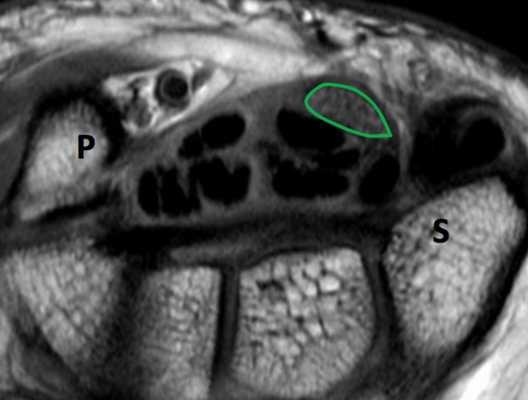

МРТ запястья. Т1-взвешенная аксиальная МРТ. Медианный нерв выделен зеленым. Р - гороховидная кость, S - ладьевидная кость.